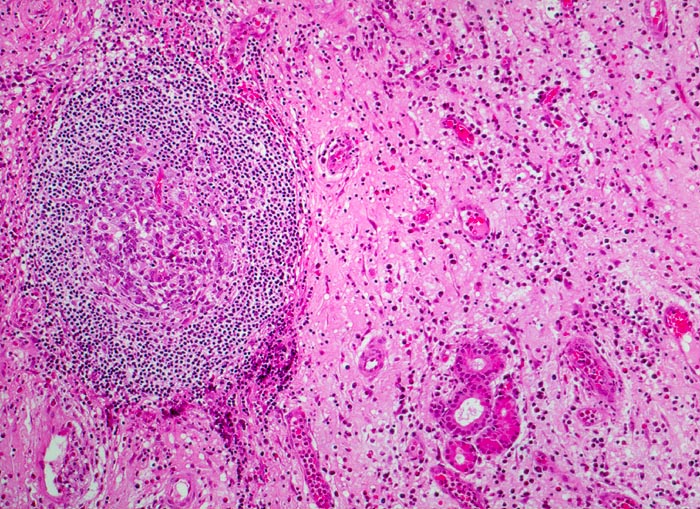

PathoPic – image database / PathoPic ID 4614 - chronische polypöse Rhinitis

chronische polypöse Rhinitis

Vermehrtes ödematöses Stroma mit spindeligen Fibrozyten und gemischtem Entzündungsinfiltrat. Lymphfollikel mit Keimzentrum. Blutgefässe gefüllt mit Erythrozyten und Entzündungszellen. Seromuköse Drüse der Nasenschleimhaut.

Patient mit nicht allergischem Asthma klagt über chronische dumpfe Kopfschmerzen und behinderte Nasenatmung. Bei der anterioren Rhinoskopie sind multiple Polypen der Nasenschleimhaut im Bereich des mittleren Meatus sichtbar.